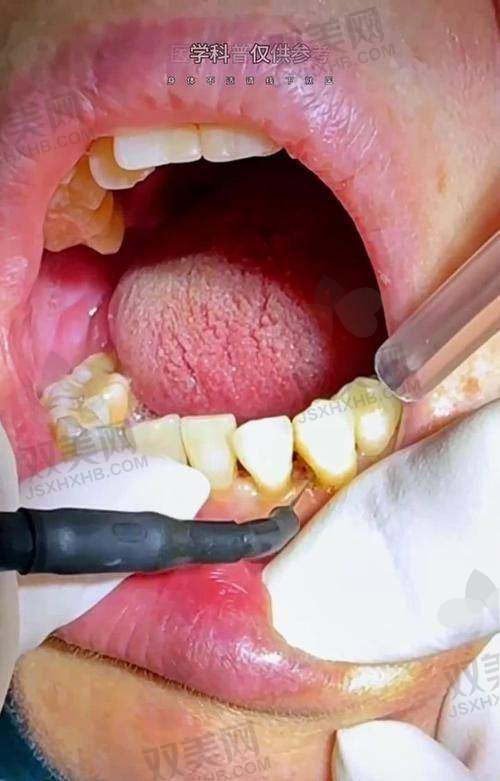

如果龋洞较浅,没有伤及牙髓,一般一次就可以完成补牙。医生会先将龋洞内的腐质去除干净,然后进行消毒,末尾填充补牙材料。整个过程大概需要30 - 60分钟。这种情况下,患者可以在较短时间内完成补牙,修复正常的咀嚼功能。